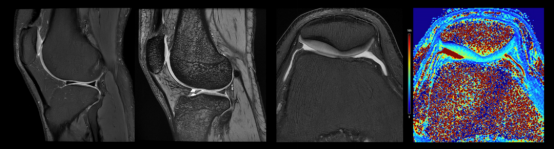

▼超高分辨关节成像▼

可进行头部、腹部、膝关节、胰腺等部位的超高分辨扫描,应用于烟雾病、帕金森病、脑肠轴、心源性卒中、肌萎缩侧索硬化(渐冻症)等的临床研究,呈现更丰富的细微结构,更精准的定量分析,助力全身疾病超早期发现。

uMR Jupiter 5T提供高信噪比、分辨率、成像速度的同时,提供丰富的高级应用,满足全身各部位的临床应用。